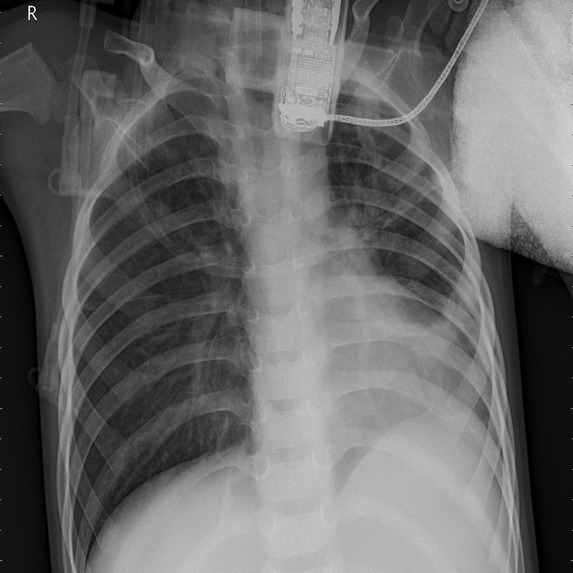

The pandemic has changed our lifestyle and until today it is affecting us, and it is necessary to know every information to keep us and our loved ones safe. With the virus mutating and increased cases of asymptomatic cases now COVID can be being detected using the chest x-rays as it affects the respiratory system first. According to LSU radiologists, these chest x-rays can be used for rapid diagnosis where there are limited testing and delayed results. And as we all know prevention is better than cure with a lot of advice from everyone there is a lot of confusion over the right and spam news. There is a need for expert advice, current news, and rapid diagnosis.

Virtual communication is the new future. In order to help the nurses, patients, and doctors in an effective way, we have created an application that predicts whether a person has COVID or not using Xray inputs from the user and giving advice on the results, The application also gives all the latest information on COVID-19, the preventions following the CDC guidelines, the statistics of COVID-19 cases, and an easy platform to contact doctors to seek advice virtually.